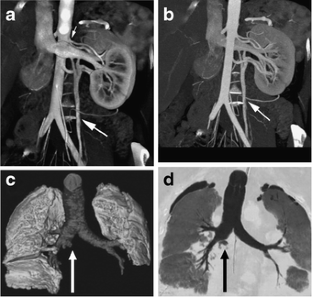

Fig 1.